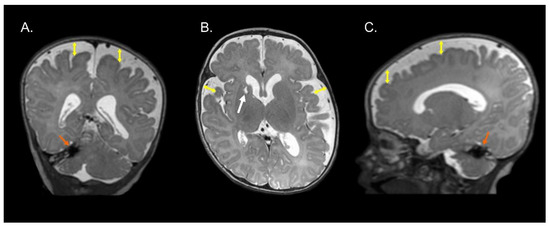

Figure 1, Figure 2 and Figure 3 show the MRI of three infants at the beginning of Katona’s treatment.

Figure 1.

Coronal (A), axial (B), and sagittal (C) T2-weighted structural MRI of a preterm infant (born at 34 gestational weeks) at 2 months of corrected age with right cerebellar hemorrhage (orange arrows) and ischemic process with cystic degeneration in head of right caudate nucleus (white arrow). Note an enlargement of the lateral ventricles (left predominance) and increase in the subarachnoid space in the fronto-temporo-parietal region (double headed yellow arrows). Images in radiological convention.